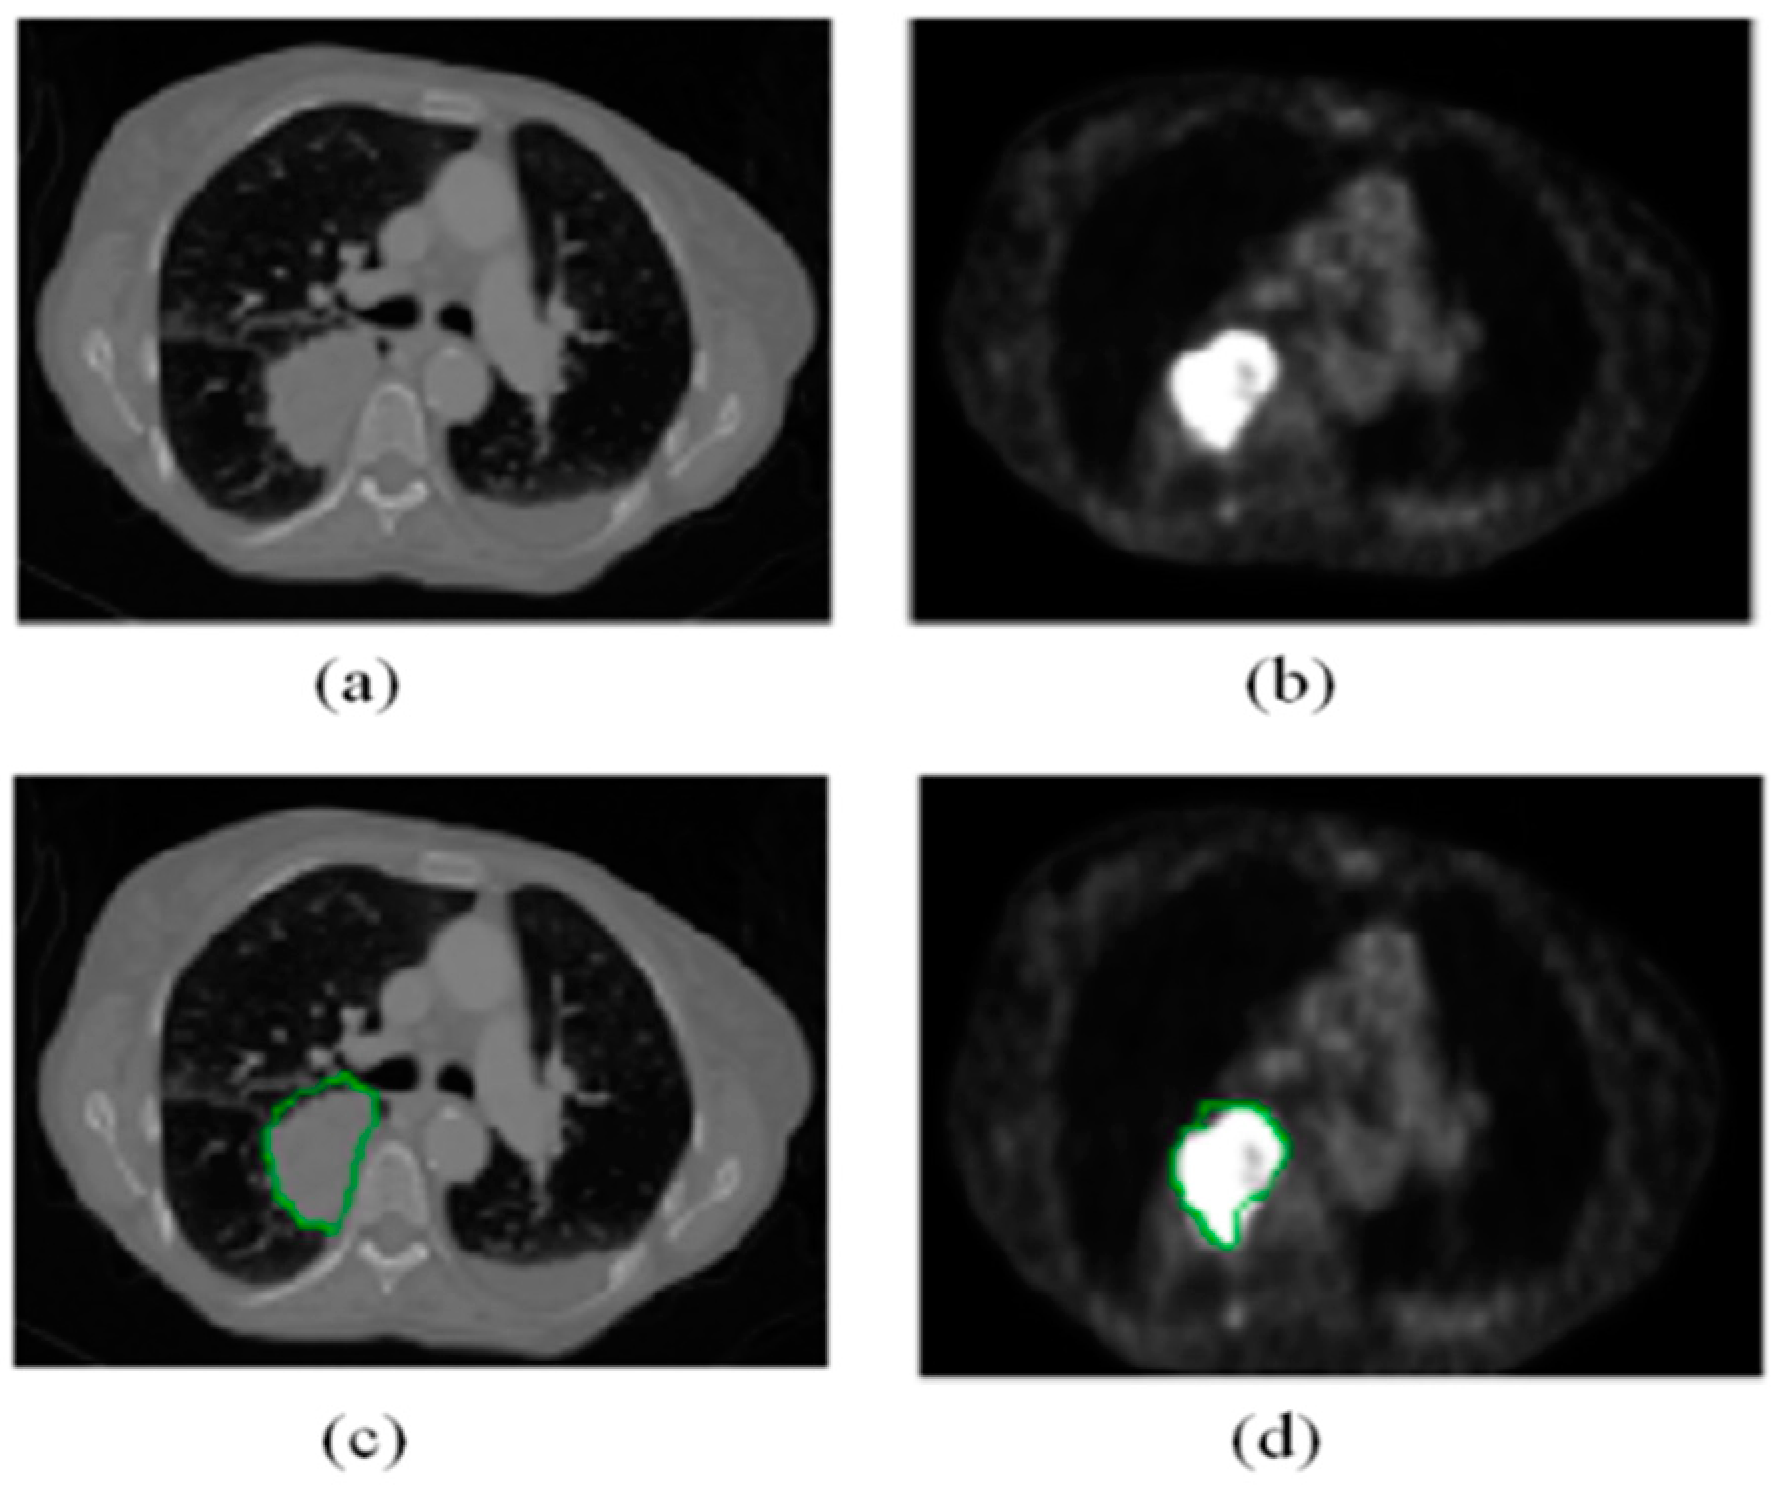

5.3.1. Mask Visualization